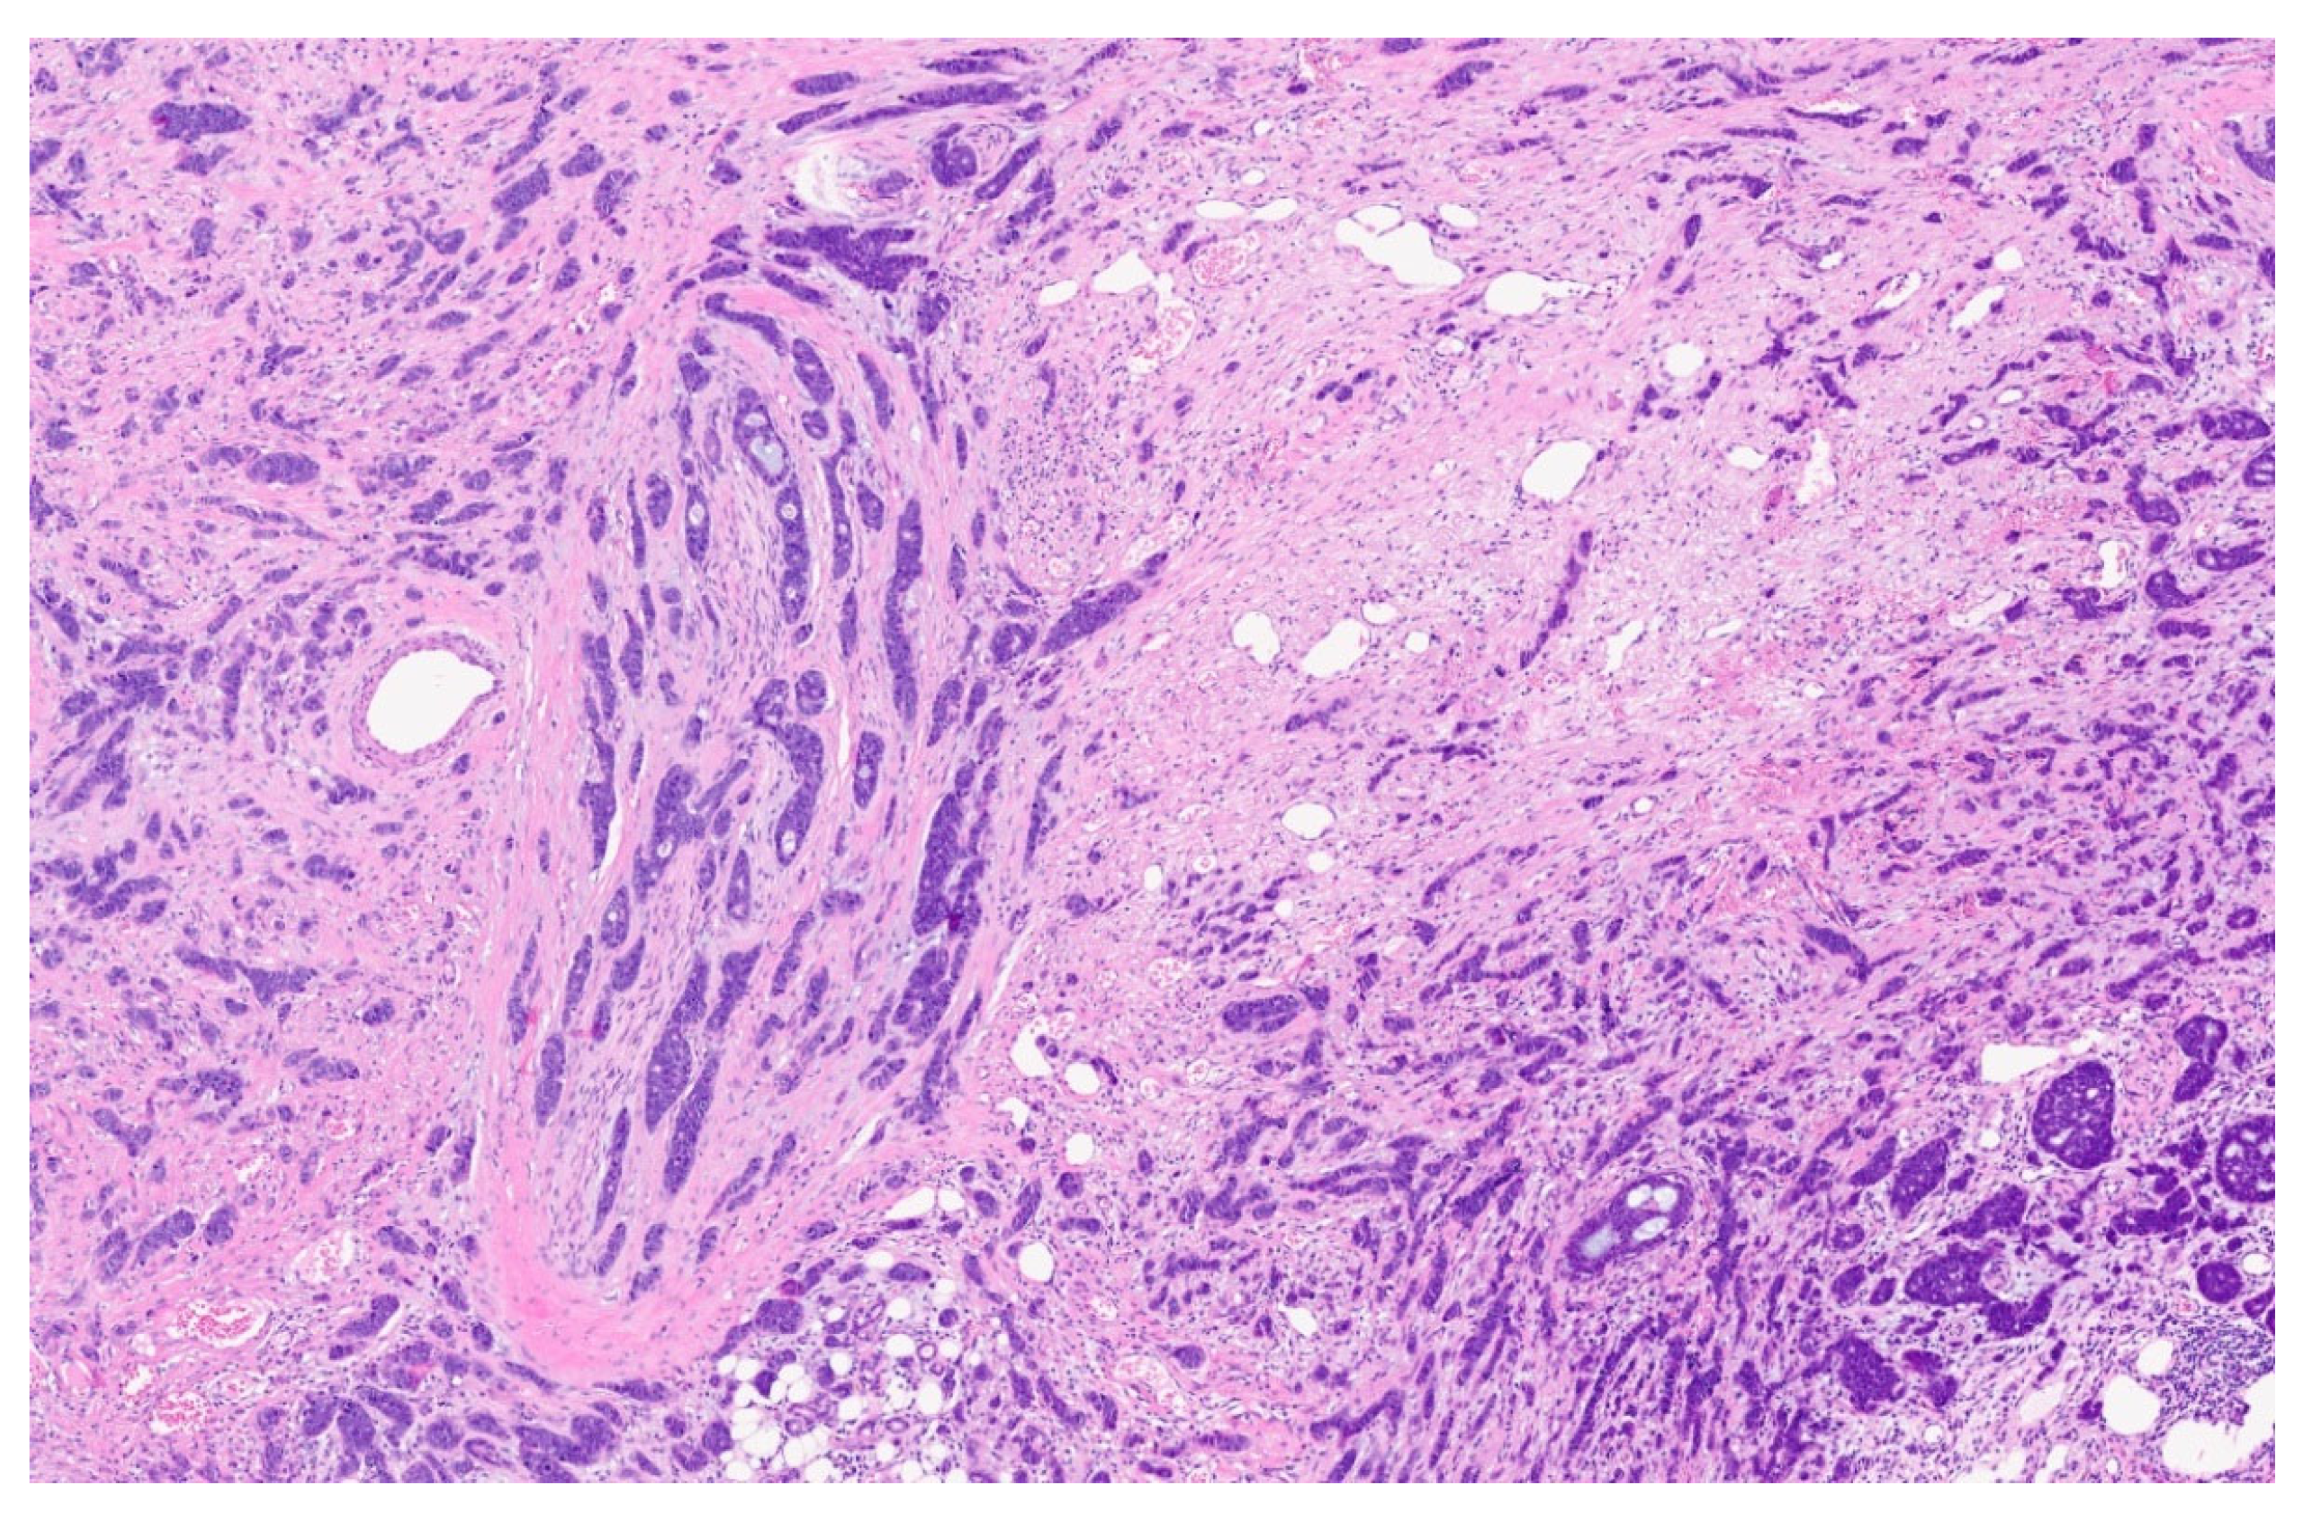

| 3 | Microlaryngoscopy with biopsy |